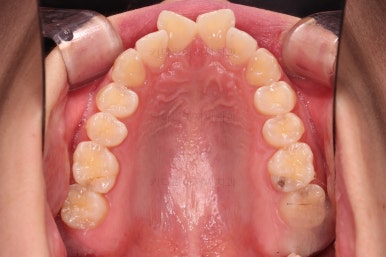

1. 초진

초진 시 입안의 모습입니다.

어금니 쪽은 약간 삐뚤긴 하지만 꼭 교정해야 할 정도는 아니고, 불편감 없이 비교적 잘 맞물리는 상태였습니다.

다만, 앞니ㅉㄱ이 공간이 부족해서 중간 치아들이 많이 회전되어있는데, 이를 환자분들의 표현에 따르면 "나비치아" 라고 부릅니다.

위아래 중간 앞니가 모두 나비치아처럼 되어있고요.

윗니가 아랫니보다 앞쪽으로 나와 있는 모습에 아래앞니가 윗니쪽으로 깊숙이 올라간 "과개교합" 양상을 보였습니다.